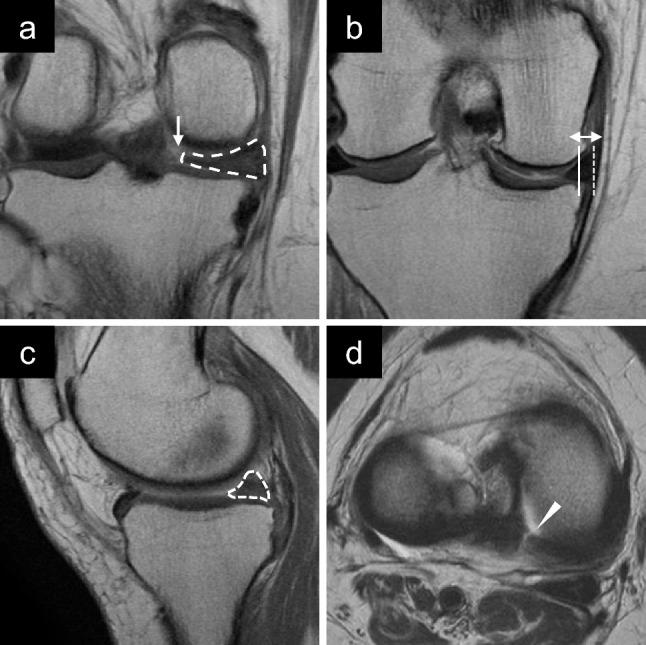

Medial meniscus (MM) posterior root tears (PRT) can lead to excessive knee loading and unsatisfactory clinical outcomes after non-operative treatment or meniscectomy. Although favourable clinical outcomes after MM posterior root (PR) repair have been reported, no study has specifically investigated the outcomes of different types of MMPRT. This study aimed to compare the clinical outcomes of patients with complete radial and oblique MMPRT following MMPR repair.

Forty patients who had undergone MMPR repair were retrospectively investigated. Patients with type 2 (20 knees) and 4 MMPRT (20 knees) were included in this study. The MMPRT type was classified according to the LaPrade classification. Plain radiographs, magnetic resonance images, arthroscopic findings, and pre- and postoperative clinical outcomes were evaluated.

回顾性调查了 40 例行 MMPR 修复的患者。本研究纳入了 20 例(20 膝)2 型和 4 型 MMPRT 患者。根据 LaPrade 分类对 MMPRT 类型进行分类。评估术前和术后的平片、磁共振成像、关节镜检查结果和临床结果。